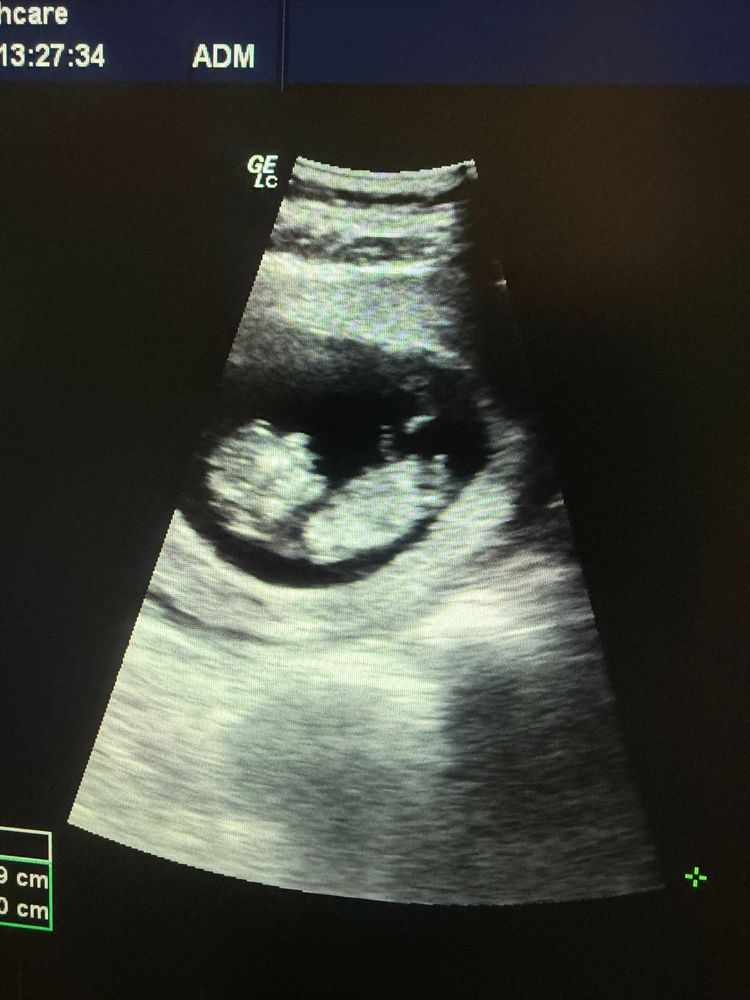

Половой бугорок

Кристина, сказала, что похож на мальчика, но я не могу понять, где там половой бугорок 😵‍💫

Мила Милова, торчит в конце туловища вверх )

Кристина, я думала, это пуповина😂